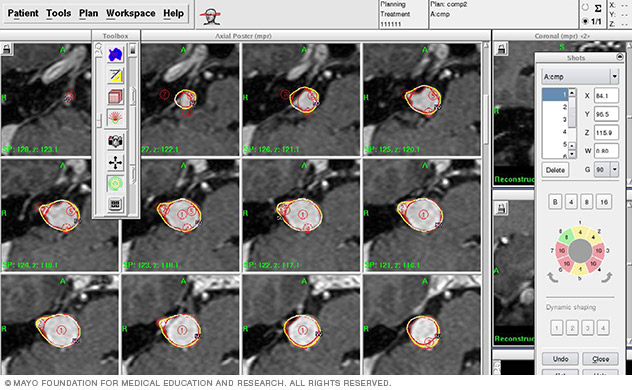

Computerized stereotactic radiosurgery radiation dose planning

Dose planning. The results of the brain scans are fed into a computerized planning system that enables the radiosurgery team to plan the appropriate areas to treat, dosages of radiation and how to focus the radiation beams to treat the areas.

This planning process may take an hour or two. During that time, you can relax in another room, but the frame must remain attached to your head. If you are doing LINAC stereotactic radiosurgery of the brain, typically you would be sent home during the planning process and treatment would be delivered a few days later.